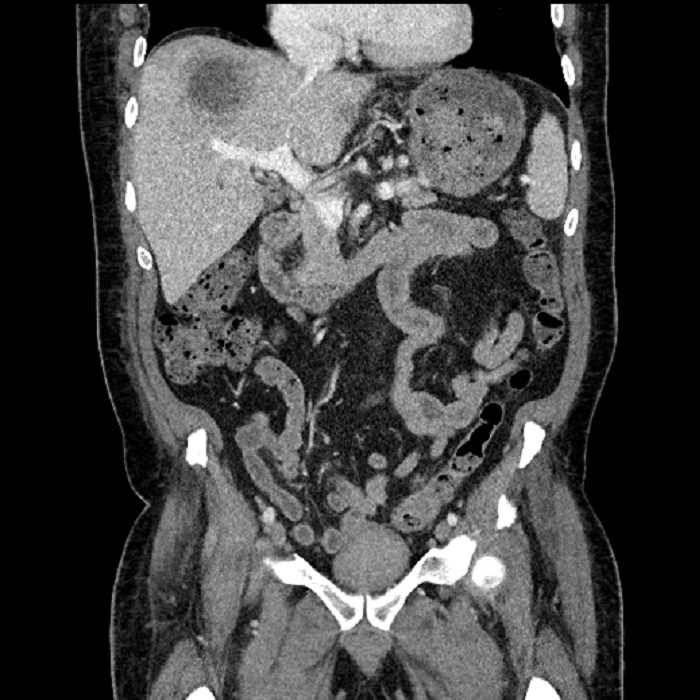

Age: 63

Sex: Male

Indication: Abdominal pain

• Large fluid density structure in hepatic segments 7 and 8 measuring 10 x 7 x 7 cm with internal septation and circumferential ill-defined low density compatible with edema

• Peripherally enhancing subcapsular collections along the anterior margin of the left hepatic lobe measuring 3 x 1 cm and 2 x 1 cm

• Clearly marginated fluid density structure in segment 7 and several other scattered tiny hypodensities, which likely represent cysts

• Hepatic abscess

Acute sigmoid diverticulitis complicated by a small contained perforation and a large abscess in the right hepatic lobe. Additional small subcapsular abscesses along the anterior margin of the left hepatic lobe.

Additionally, loss of the normal fat plane between the peridiverticular collection and adjacent thickened loops of small bowel raises the potential for an enterocolonic fistula.

• The classic CT imaging appearance is a double target sign with internal low density surrounded by an internal enhancing rim (capsule) and a low density external rim (edema)

• Abscesses may be unilocular or multilocular

• Gas is present in a minority of cases

• Unfortunately, necrotic tumors can have an overlapping imaging appearance, so it is important to follow these to resolution

Hepatic abscess showing the double target sign with low density internally surrounded by a thin inner enhancing rim (red arrow) and ill-defined outer low density rim (yellow arrow). Blue arrow indicates an internal septation. Red arrows: additional smaller subcapsular abscesses. Red arrow: focal contained perforation associated with diverticulitis.